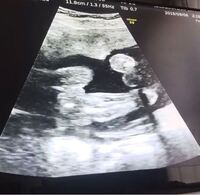

妊娠12週目 12w0d 6d のエコー写真とエピソード 妊娠4ヶ月 Cozre コズレ 子育てマガジン